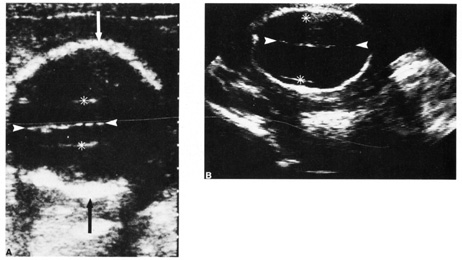

Traditional genetic amniocentesis is usually offered between 15 and 20 weeks' gestation. Amniocentesis performed earlier has a higher complication rate, as well as more amniotic culture failures. It may be offered when prenatal maternal screening results are high risk for a genetic abnormality or as an elective diagnostic test such as in advanced maternal age or prior history of an aneuploidy (see Fig. 2).

Fig. 2. Left midabdomen of neonate shows indented area probably resulting from contact of the amniocentesis needle with the abdominal skin.

Many large, multicenter studies have confirmed the safety of genetic amniocentesis, as well as its cytogenetic diagnostic accuracy (greater than 99%).2 The fetal loss rate is approximately 0.5%, and minor complications occur infrequently. Table 4 lists known complications for amniocentesis.

Needle injury rare (Fig. 2)

The procedure is performed under ultrasound guidance. After obtaining informed consent, an ultrasound examinations is performed to establish fetal viability, placental and fetal location, and depth to the largest pocket of amniotic fluid (Fig. 3). The maternal abdomen is prepped aseptically and a local anesthetic may be administered. A small gauge needle is then used to aspirate approximately 10 to 20 mL of amniotic fluid. The availability of the results is dependent on the amount of time needed for cell culture growth but usually is available within 7 to 10 days. The results received are a full cytogenic karyotype.

Fig. 3. A and B: Withdrawal of amniotic fluid with 20-gauge needle and 30-mL syringe.